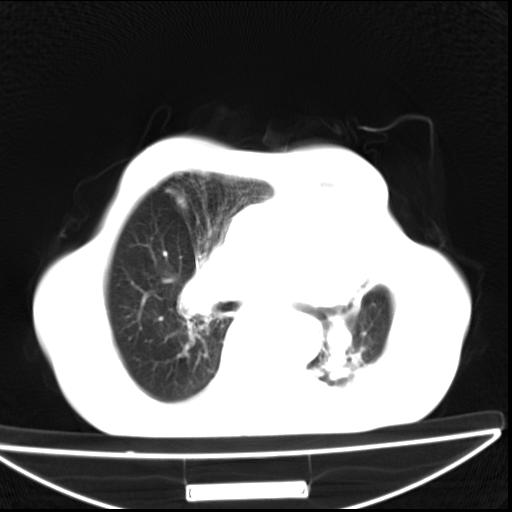

男  70岁,发烧咳嗽4天。盗汗,消瘦。无痰中带血丝,以前有肺tb病史,ct见,双肺tb,左侧胸廓塌陷,左胸膜肥厚粘连。纵隔移位,右侧胸腔积液,大家说说那个心影前左肺舌叶除了肺大炮还有炎症还是干酪性肺炎?有占位吗?我看纵隔淋巴结也大。

双肺继发性肺结核伴部分左肺毁损!

1)两肺继发性肺结核并左肺上叶肺不张,支气管扩张。2)双侧胸膜炎(胸膜增厚+少量胸腔积液)。

两肺继发性肺结核并感染,左肺上叶肺不张。建议ct增强。